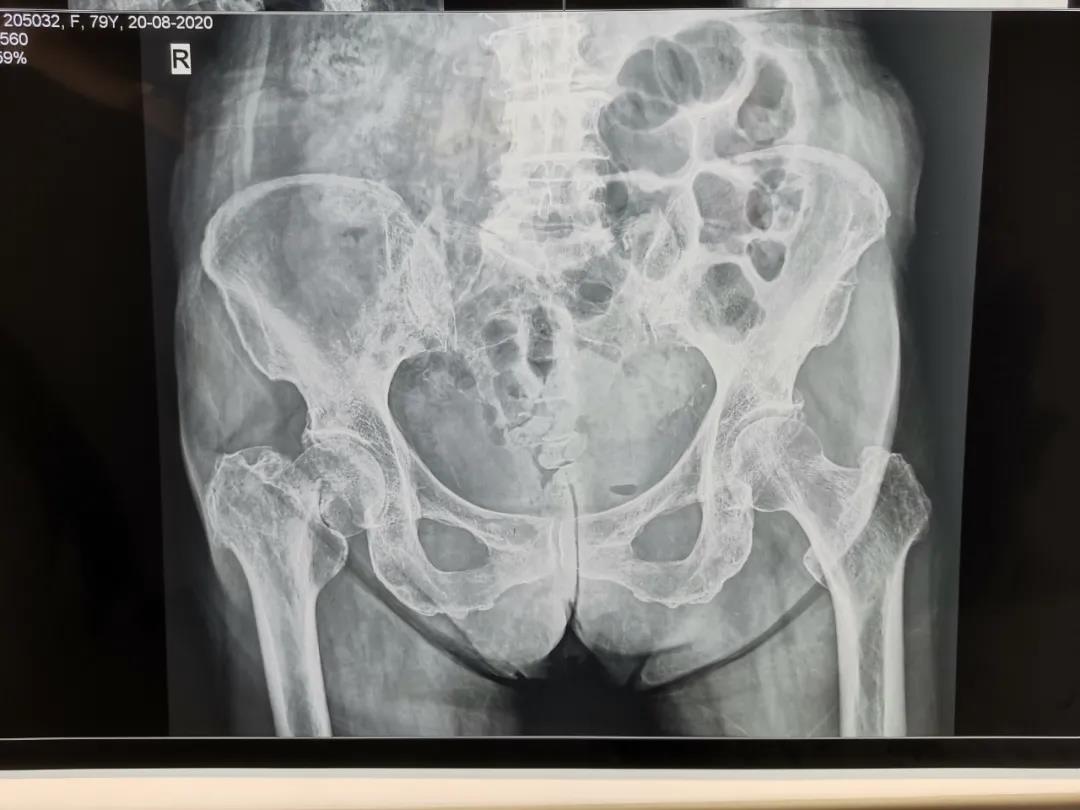

人工股骨頭置換手術(shù)治療老年股骨頸骨折

股骨頸骨折是老年骨質(zhì)疏松性骨折最常見的一種髖部骨折,是老年患者致殘和致死的主要原因之一,發(fā)生髖部骨折后1年內(nèi),20%的患者會(huì)死于各種并發(fā)癥,約50%的患者致殘,生活質(zhì)量明顯下降。骨折后病人往往因肢體疼痛、不能行走致長期臥床,部分骨折的病人還伴有全身基礎(chǔ)疾病,如果病人能夠盡早下地活動(dòng),減少臥床時(shí)間,就能有效減少臥床并發(fā)癥發(fā)生。為達(dá)到這個(gè)目的,越來越多的病人選擇了手術(shù)治療。對于老年人的股骨頸骨折而言,較好的手術(shù)方式是人工髖關(guān)節(jié)置換術(shù)。

79歲的杜大娘在家不慎摔倒,跌傷右髖部,許冬雷主任為其主刀行右股骨頸骨折人工股骨頭置換術(shù),用時(shí)短,出血少,患者清醒后就說腿不疼了,術(shù)后第一天見到醫(yī)生就豎大拇指,激動(dòng)地說:“手術(shù)前我很害怕、也很焦慮,沒想到手術(shù)后一點(diǎn)也沒有感覺到疼痛”。術(shù)后第3天就可以下地活動(dòng)了,老人的生活又恢復(fù)了往日的悠然自在。

骨二科采用人工半髖關(guān)節(jié)置換(高齡身體基礎(chǔ)差患者)或人工全髖關(guān)節(jié)置換(相對年輕,身體條件較好患者)能夠迅速恢復(fù)患者的下床行走及生活自理能力,避免長期臥床引起的并發(fā)癥,減輕患者家屬的護(hù)理負(fù)擔(dān),提高患者的生活質(zhì)量,是治療老年股骨頸骨折首選治療方案。